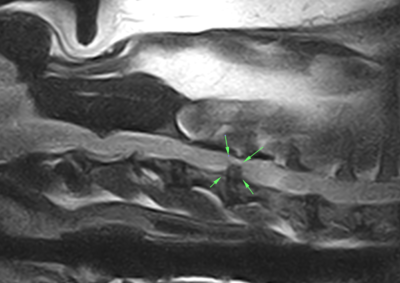

脳神経外科 注意 ボタンをクリックした先に、治療中および手術中の画像が説明で使用されている場合がございます。 そのような画像に弱い方は閲覧なさらないようお願いいたします。 脳神経外科 Ventral Slot 脳神経外科 椎間板ヘルニア 脳神経外科 PLDD 多発性頸部椎間板ヘルニア 脳神経外科 椎間板ヘルニア 脳神経外科 経皮的レーザー椎間板除圧術 PLDD 脳神経外科 椎間板ヘルニア 脳神経外科 環軸椎不安定症に対する環軸固定術 脳神経外科リハビリテーション… 脊髄梗塞 脳神経外科 ベントラルスロット 脳神経外科 ベントラルスロット 脳神経外科 環軸不安定症 脳神経外科内科 Feline Meningoencephalomyelitis of Unknown Origin : 猫の... <1234567> 症例カテゴリー 放射線治療整形外科軟部組織外科脳神経外科内科腫瘍外科救急・集中治療リハビリテーション科腫瘍内科内視鏡科脳神経科呼吸器外科中医・漢方猫の腎移植循環器科